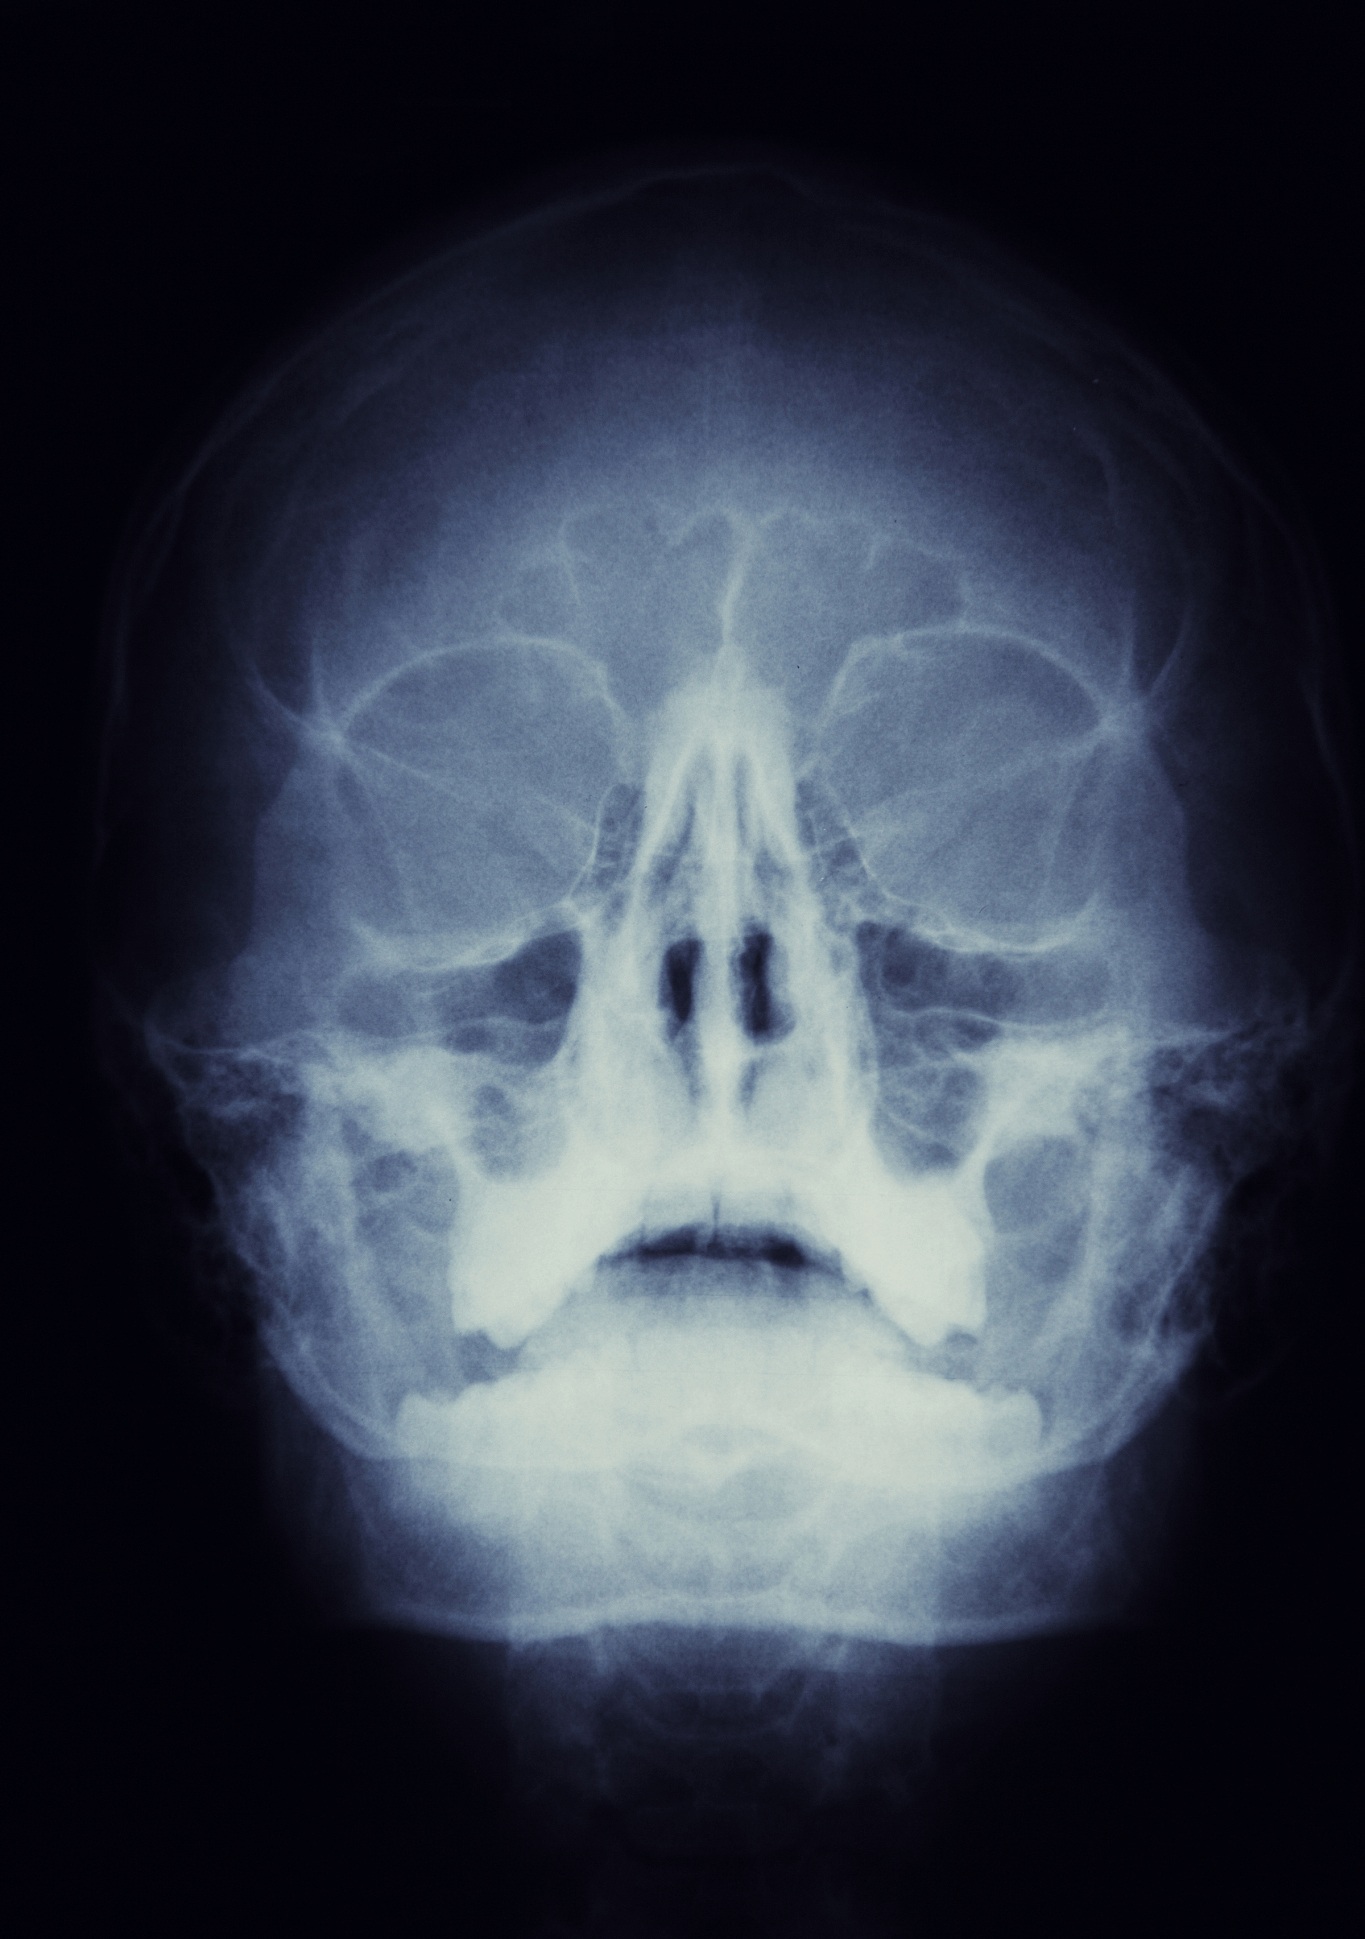

3、医学影像管理

用于会诊相关医学影像的采集、储存、处理、诊断,专家在进行远程会诊时,可以通过该模块调取患者患处医学影像数据,并讨论给出诊断结果和指导意见。